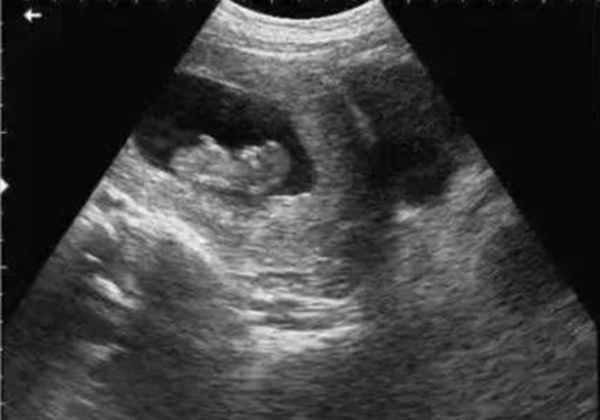

• 超声检查(B超/彩超):它利用超声波的反射原理成像,就像“用声音给身体拍照片”,没有任何辐射。无论是孕期产检(观察胎儿发育)、腹部检查(排查肝脾胆囊问题),还是甲状腺、乳腺等浅表器官检查,超声都是首选。而且超声检查灵活便捷,还能实时动态观察器官运动(比如心脏跳动、胎儿胎动),是临床中应用最广泛的“安全检查”。